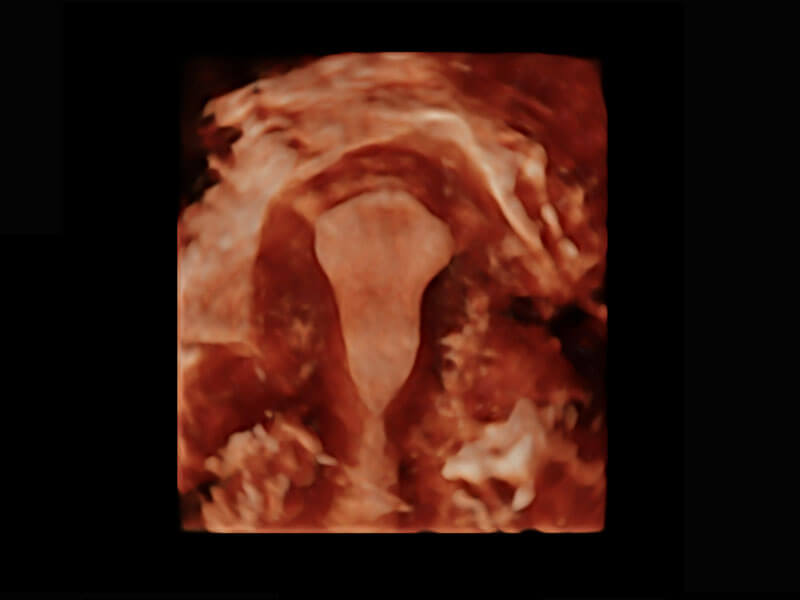

腔内三维-光影成像

P60搭载一系列胎儿心脏成像技术,实现精细的胎儿心脏评估。

四腔切面

四腔心血流

右室双出口

胎心容积成像